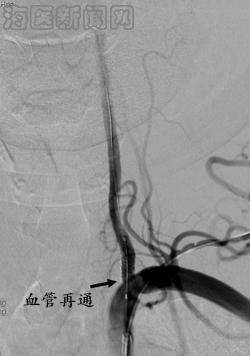

病例1 黄某某,女,70岁,因为“头晕伴呕吐半月”入院,既往有糖尿病病史。术前不能头晕下床,造影发现左侧椎动脉开口重度狭窄,予以支架置入术,血管再通。已随访2年6月,目前无头晕症状,能出国旅游。

治疗之前,左侧椎动脉重度狭窄 治疗之后,左侧椎动脉完全开通